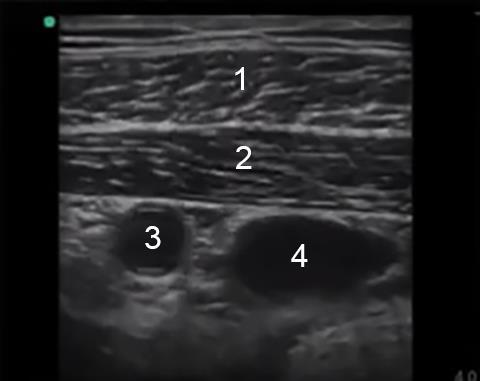

1. Musculus pectoralis major

2. Musculus pectoralis minor

3. Arteria axillaris

4. Vena axillaris